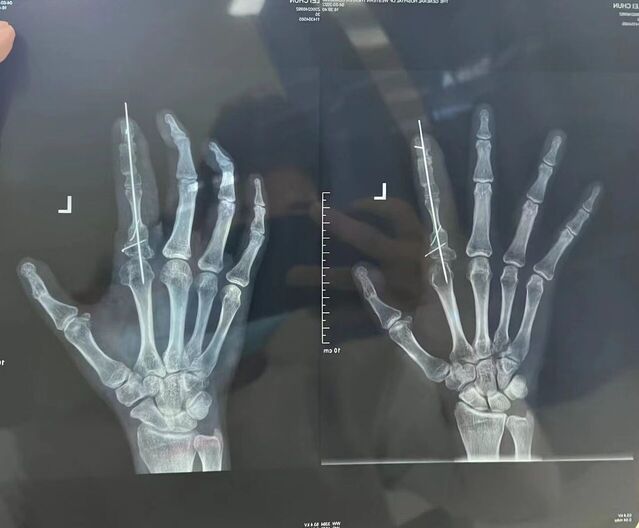

示指长手指再造。术后1年随访